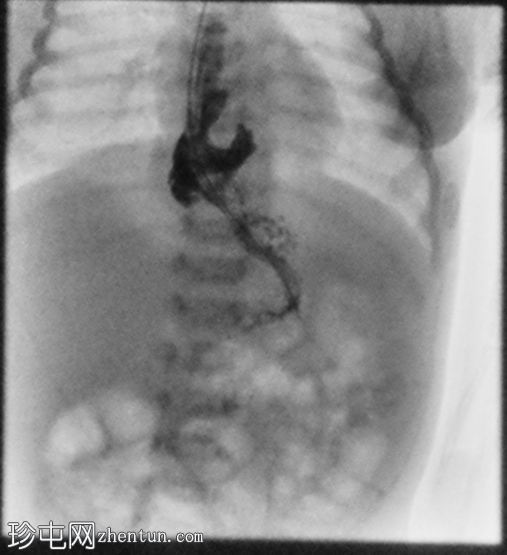

正位

胃部初始显影,并立即反流至食管裂孔疝。在其近端可见管径正常的远端食管。十二指肠降部和横部显影较弱,左上腹可见数段管径较小/部分减压的近端小肠显影。

延迟1小时拍摄的X线片显示食管裂孔疝和胃部仍有造影剂残留,造影剂远端扩散受限,很可能是由于造影剂用量较少所致。充满气体的肠袢外观正常,乙状结肠内可见气体,直肠内未见气体。